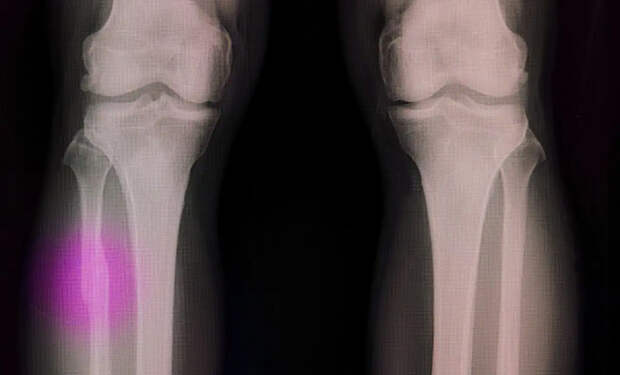

Исследователи из Университета Сунгкюнгван модифицировали инструмент так, чтобы он создавал костные вставки прямо на месте перелома. Эксперименты на кроликах с тяжелыми переломами бедра показали: через 12 недель после операции животные, получившие новые «распечатанные» вставки, восстанавливали кости быстрее и без признаков инфекции. Для сравнения — у кроликов с традиционными цементными вставками результаты были хуже.